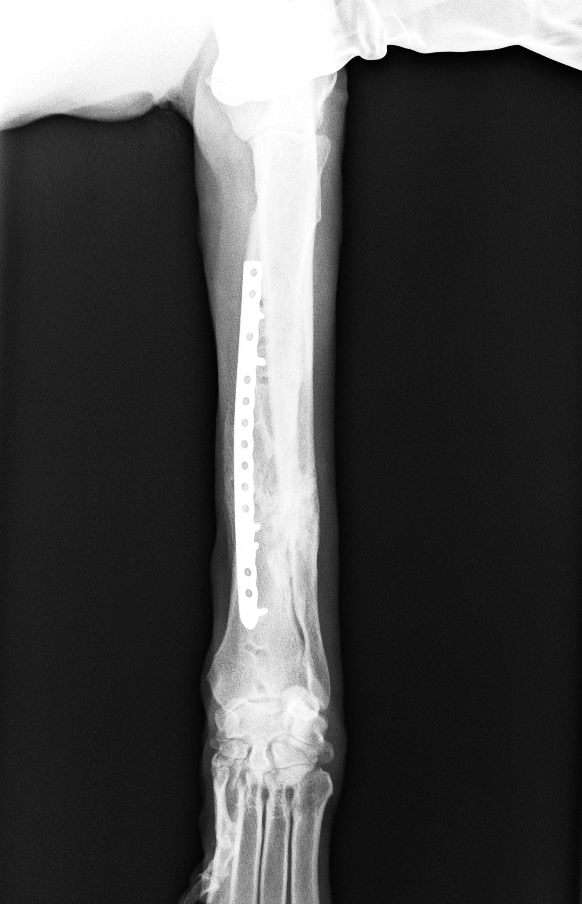

脛骨粗面成長板骨折